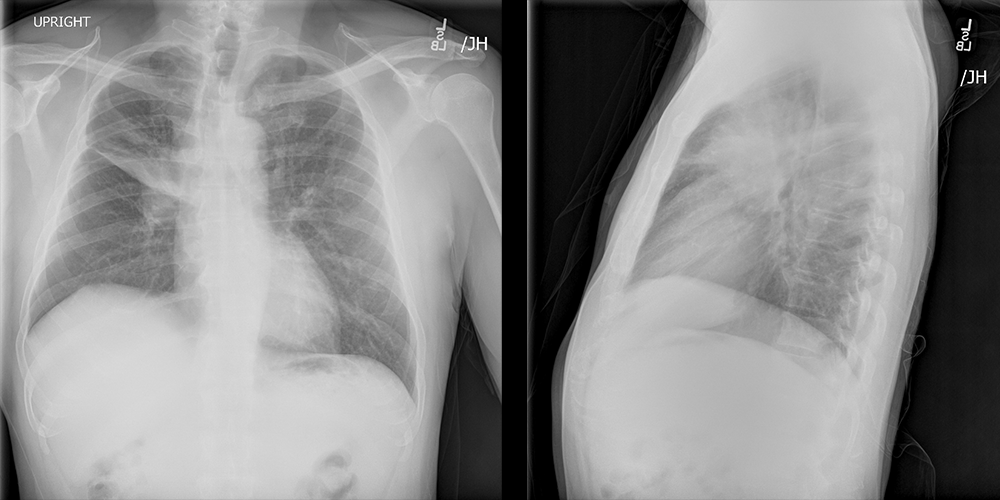

PA and lateral chest X-ray

What best describes the findings on the chest x-ray?

There is a large mass lesion near the hilum of the right lung. Its large size is highly concerning for malignancy. There is also atelectasis of the anterior portion of the right upper lobe. These findings represent atelectasis and not airspace opacifications considering the superior displacement of the minor fissure, absence of air bronchograms, and absence of fluffy infiltrates with indistinct borders.